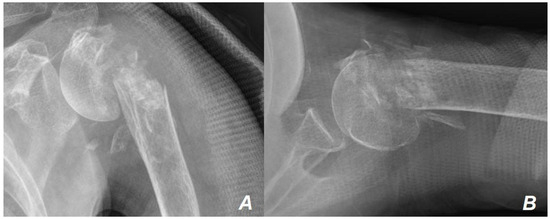

2. Case Presentation

Surgical Technique